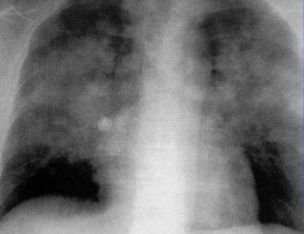

5.患者入院时胸片正常,突发心跳骤停,气管插管时喉痉挛,解除痉挛后,复查胸片如下:

这个蝶翼征太夸张,像是雄鹰展翅。小小竹排江中游,巍巍青山两岸走,雄鹰展翅飞,哪怕风雨骤!

为什么会突然这样?

原来,肺水肿的原因多如牛毛。喉痉挛时气道阻塞,胸腔内负压增加,痉挛解除后,胸腔内负压减少,血管内外压力差值增加,引起肺水肿。